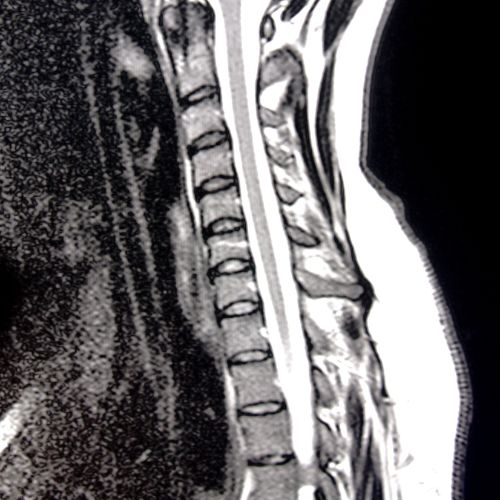

Our 1.5 T MRI machine should provide a convenient and comfortable scanning experience for obese and claustrophobic patients.

Stavya offers complete spine diagnostics under one roof combining advanced imaging, accuracy, and patient comfort.

Detailed assessment for surgical planning.